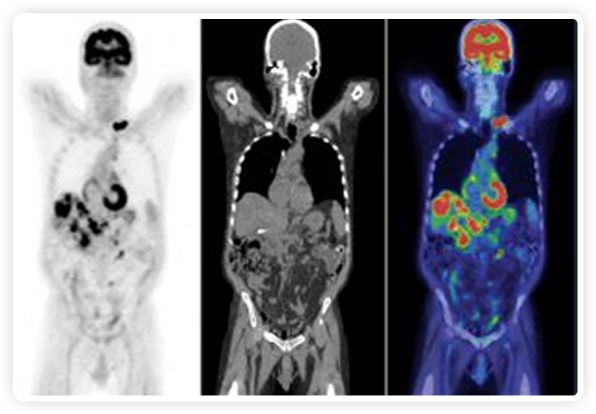

正電子發(fā)射斷層掃描(PET)是癌癥檢測中已建立的成像標準,與其他成像方式相比,PET能提供高靈敏度和特異性的圖像。

到目前為止,放射腫瘤學中(使用的圖像主要是結構性的,而PET圖像可以提供生物學信息。通過使用注射示蹤劑,例如18-FDG,PET可以描繪腫瘤的代謝活性,使其“點亮”。(FDG是用于可視化癌癥代謝的最廣泛使用的示蹤劑。與正常組織相比,腫瘤細胞保留更高水平的FDG。)不同的PET示蹤劑可以識別腫瘤的不同生物學特征,例如特定生物標志物抗原(例如,PSMA)或甚至探測免疫系統(tǒng)本身(例如,PDL1表達或活化的T細胞)。

PET+放療共同治療

RefleXion將PET成像與立體定向放射治療相結合。在注射示蹤劑后,RefleXion的技術基于示蹤劑信號實時地在一個或多個目標上引導治療性X射線。使用這種專有方法,RefleXion的平臺有可能比現(xiàn)有系統(tǒng)向癌癥病變提供更高劑量的輻射,并改善周圍健康組織的保護。